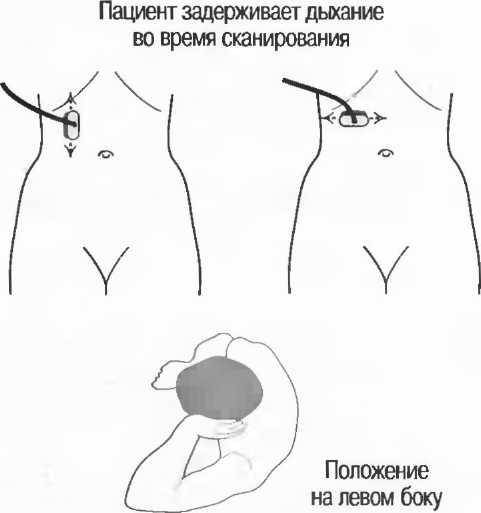

1. Подготовка

Пациент не должен пить и есть в течение 8 ч перед исследованием. Если жидкость необходима для предотвращения дегидратации, можно давать пациенту только воду. При острой симптоматике исследование можно проводить без подготовки. Детям, если позволяют клинические условия, пища и вода не даются в течение 3 ч до исследования.

При более углубленном исследовании, если нет клинических противопоказаний, может быть полезным дополнительный прием воды, особенно при исследовании поджелудочной железы, нижних отделов живота и таза.

2. Положение пациента. Пациент может лежать в удобной позе на спине. Под голову можно положить маленькую подушку, в случае выраженного напряжения передней брюшной стенки подушечку можно поместить также под колени пациента.

Намажьте живот гелем.

Пациенту разрешается дышать спокойно, однако при исследовании отдельных органов требуется задержка дыхания на вдохе.

3. Выбор датчика. Используйте датчик 3,5 МГц для взрослых и датчик 5 МГц для детей и худых взрослых. Предпочтительны конвексные или секторные датчики.